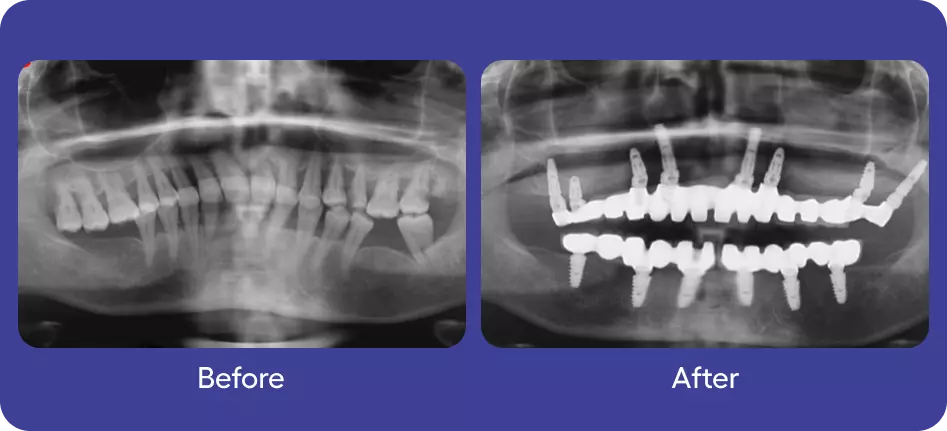

Implants

Full Mouth Rehabilitation